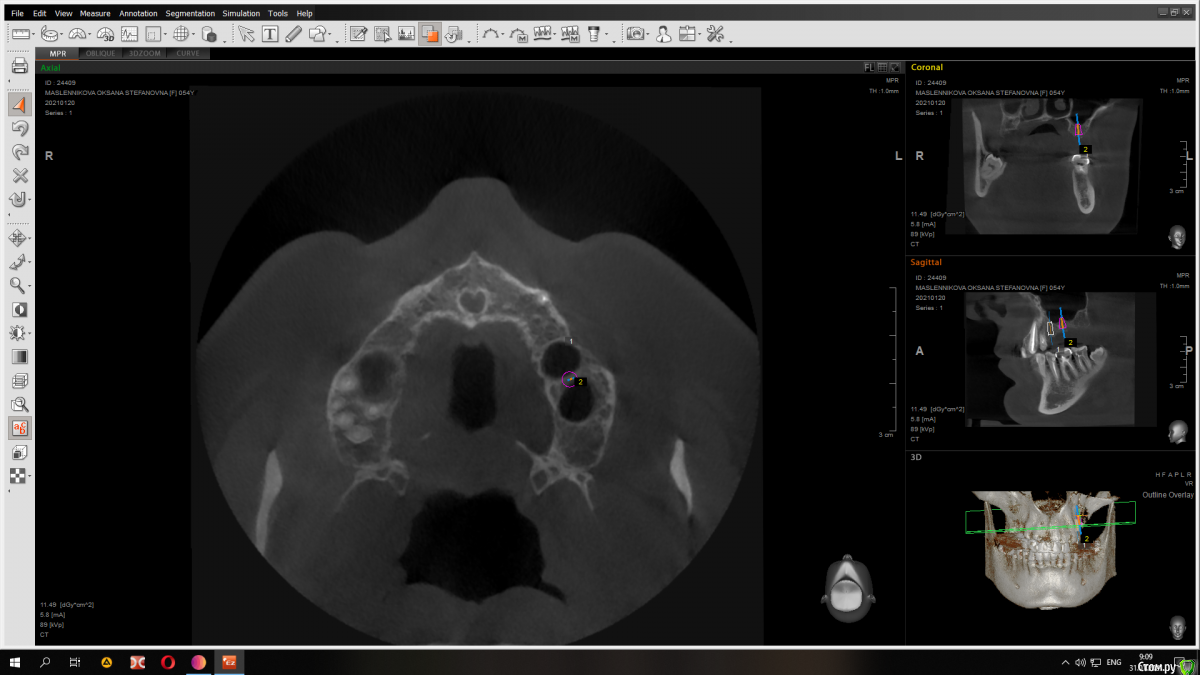

Raystom Опубликовано 31 января, 2021 Автор Поделиться Опубликовано 31 января, 2021 Конечно) Вот вариант с 8.5 мм имплантатом Ссылка на комментарий

red_butler Опубликовано 31 января, 2021 Поделиться Опубликовано 31 января, 2021 Имхо замеры сделаны не правильно, но не вижу проблем. Если нет остеотомов, то закрытый синуслифт можно выполнить имплантом 1 Ссылка на комментарий

Raystom Опубликовано 31 января, 2021 Автор Поделиться Опубликовано 31 января, 2021 Имхо замеры сделаны не правильно, но не вижу проблем. Если нет остеотомов, то закрытый синуслифт можно выполнить имплантом в чем ошибка в замерах? Ссылка на комментарий

red_butler Опубликовано 31 января, 2021 Поделиться Опубликовано 31 января, 2021 в чем ошибка в замерах?замеры используя шаблон импланта Ссылка на комментарий